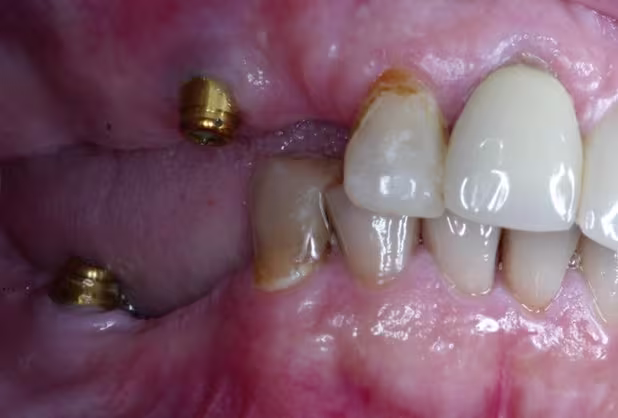

The diameter, length, number, antero-posterior spread, axial inclination, and the location of the implant must be carefully planned, as each factor affects load distribution and long-term outcomes.45 The position of the implant should be optimized in all three dimensions. Placing the implant apically may create unfavorable vertical cantilevers, while buccolingual or mesiodistal mispositioning (Figure 19) can result in lateral cantilevers and uneven load transfer. Comprehensive planning is critical for establishing a stable and biomechanically favorable occlusion.

Figure 19. Suboptimal implant positioning in the vertical and mesiodistal planes.